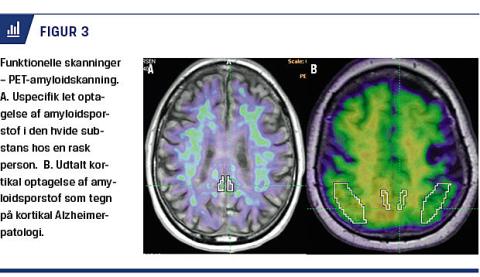

Alle personer, som undersøges for kognitiv dysfunktion, skal udredes med strukturel skanning. Det væsentligste formål med strukturel skanning i forbindelse med basal udredning er: 1) at udelukke andre, behandlelige årsager, f.eks. intrakranial tumor, blødninger (f.eks. subduralt hæmatom) eller hydrocefalus og 2) at afsløre eventuelle vaskulære læsioner (infarkter eller iskæmiske skader) som årsag til den kognitive dysfunktion. Det er også muligt – selv med CT – at påvise specifikke neurodegenerative forandringer (lokaliseret atrofi), der kan lede til diagnosen [2, 3]. Især kan atrofi af de mediale temporallapper understøtte diagnosen Alzheimers sygdom (AS). Denne atrofi kan bedst påvises på koronale snit (Figur 1). CT kan således anvendes som led i basal udredning, men MR-skanning giver ofte supplerende oplysninger. Sensitivitet og specificitet af kliniske diagnosekriterier for AS over for andre demenssygdomme på baggrund af ovenstående basale udredningsprogram er i en metaanalyse fundet at være hhv. 79% og 73%, når referencen er histopatologisk verificering af AS-patologi [4].

MR-skanning giver bedre mulighed for at vurdere lokaliseret atrofi og iskæmiske læsioner, end CT gør, men kun i få studier har man sammenlignet de to skanningstyper hos relevante patientgrupper. I en stor metaanalyse fandt man MR-skanningssensitivitet og -specificitet for AS i blandede demenspopulationer på hhv 88% og 77% [4]. Det kan anbefales at anvende MR-skanning hos yngre personer eller ved atypiske forløb eller symptomer. Både atrofi (især af den mediale temporallap på koronale snit) og subkortikale vaskulære læsioner kan med fordel vurderes ved hjælp af simple visuelle skalaer [3], således at bedømmelsen af disse standardiseres, når de videreformidles fra radiologer til de udredende læger.